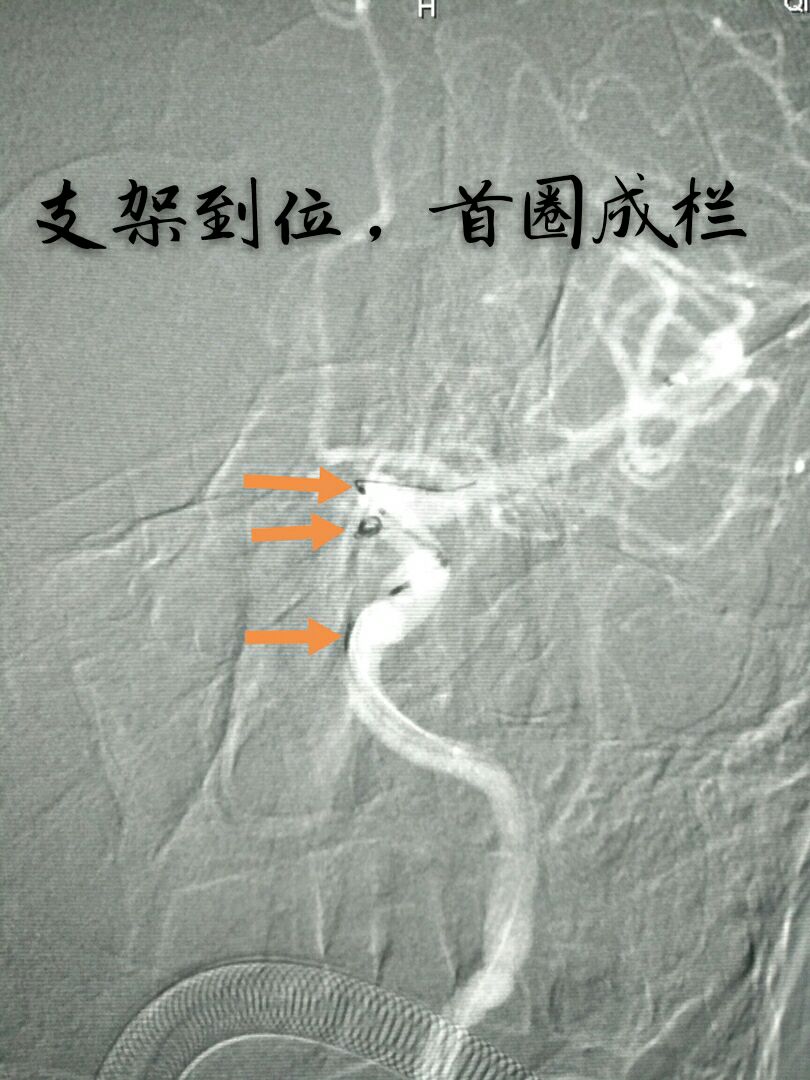

病例十:老年男性患者,间断性头痛1年,DSA示左侧颈内动脉后交通段动脉瘤,后交通动脉从瘤颈部发出

支架打开,首圈完美成栏